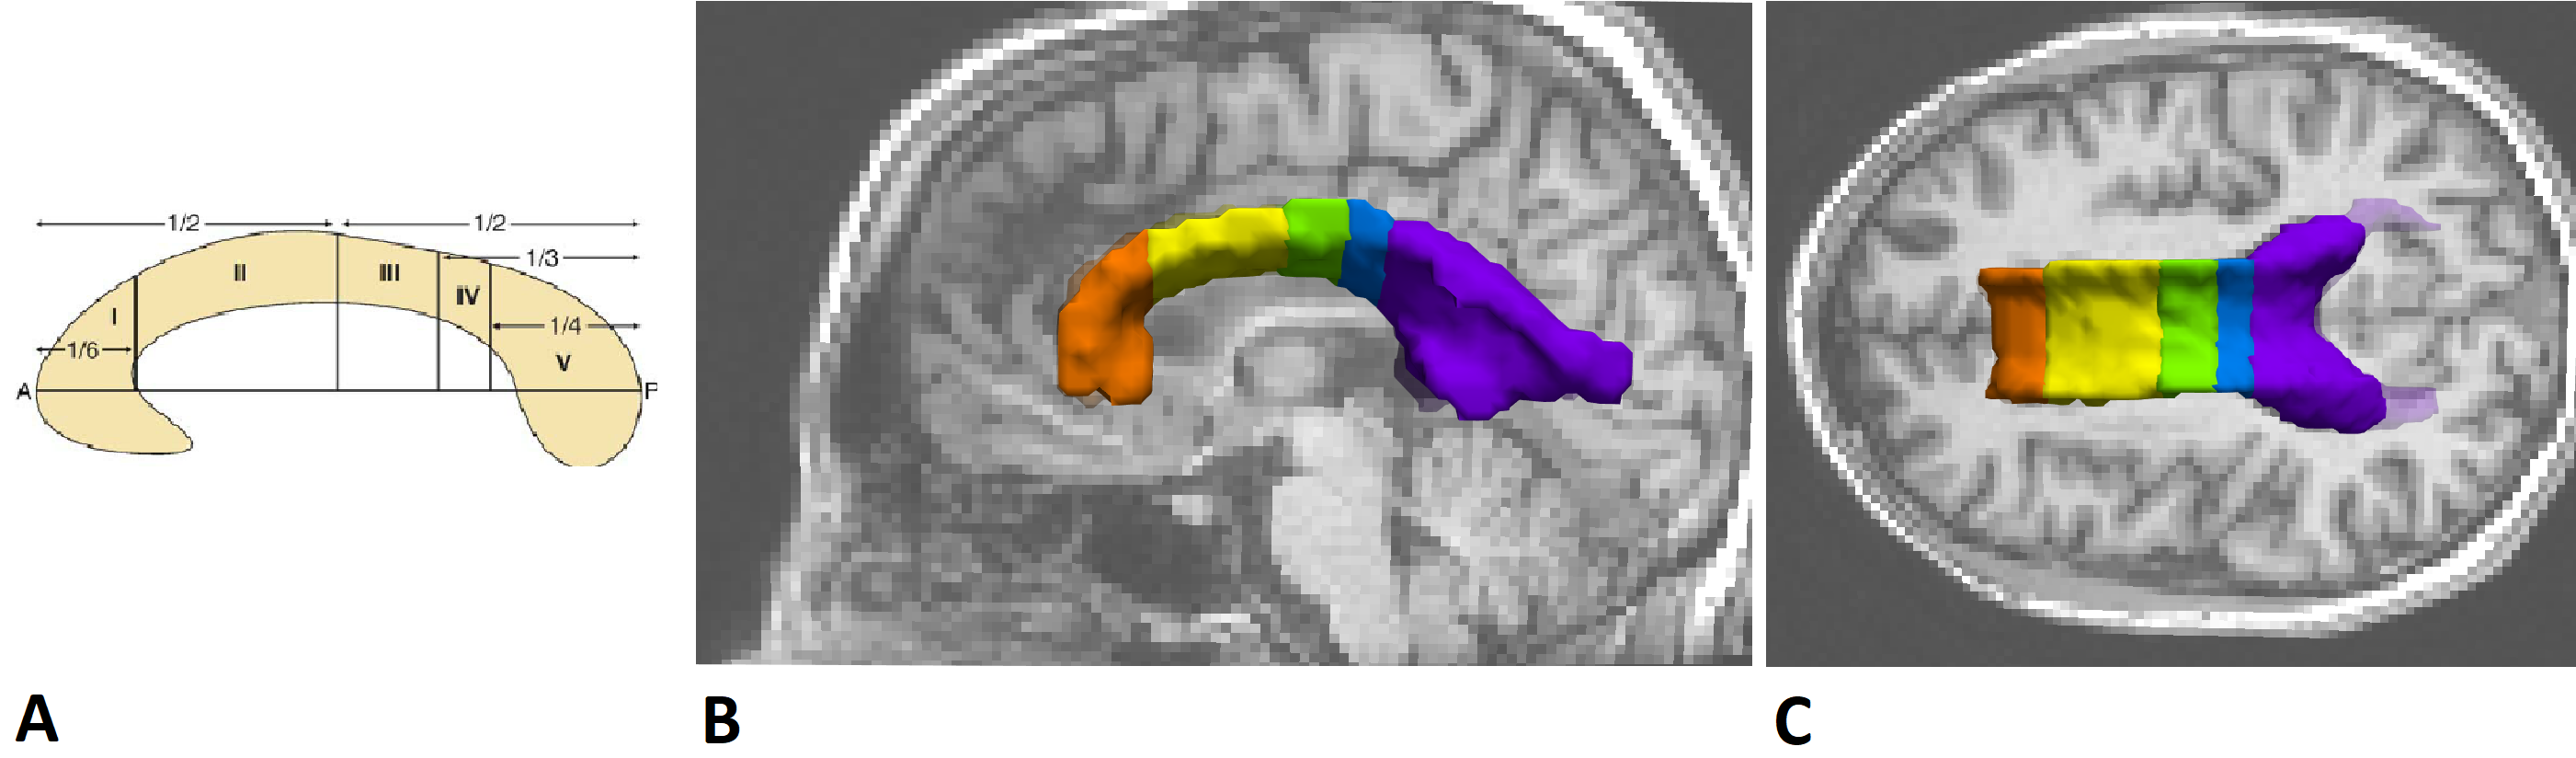

1. Corpus_callosum_division.py: Code to obtained a subdivision of the CC.